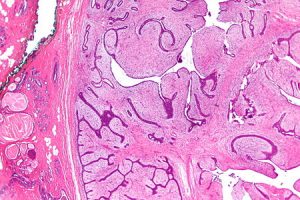

• معظم سرطانات الثدي تبدأ في القنوات التي تحمل الحليب إلى الحلمة وتسمى سرطانات الأقنية.

• يبدأ بعضها في الغدد التي تصنع حليب الثدي وتسمى سرطانات مفصصة.

المرحلة 0: المعروفة باسم سرطان الأقنية في الموقع (DCIS)، حيث يقتصر وجود السرطان في هذه المرحلة داخل القنوات ولم ينتشر في الأنسجة المحيطة.